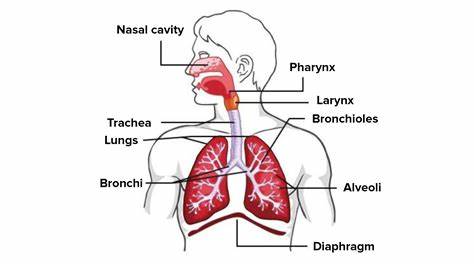

The Respirtory System

The respiratory system is your body’s built-in air pump, and its main function is to ensure oxygen reaches your cells while removing carbon dioxide. Here’s how it works:

- Breathing (Ventilation): Your lungs expand and contract, pulling oxygen in and pushing carbon dioxide out.

- Gas Exchange: Oxygen from the air you breathe moves into your bloodstream, while carbon dioxide, a waste product, is expelled when you exhale.

- Oxygen Delivery: The oxygen-rich blood is transported throughout your body to fuel essential functions.

- Carbon Dioxide Removal: Your body gets rid of carbon dioxide, preventing toxic buildup.

- Speech & Smell: Air passing through your vocal cords allows you to speak, and the nasal cavity helps detect smells.